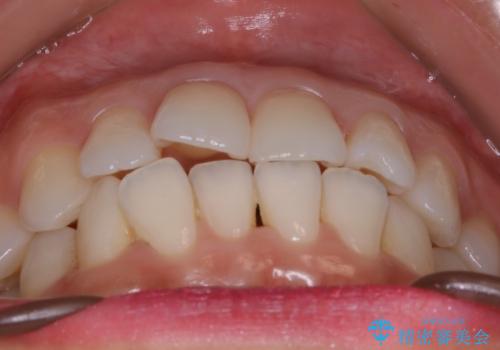

【非抜歯】前歯のガタつき マウスピースの部分矯正

- 上下の前歯の細かいガタつきの治療をご希望されて来院されました。

奥歯部分にはガタつきや噛み合わせの問題などがほとんど見られず、前歯のガタつきも軽度だったため、インビザライン ライト パッケージでの部分矯正を行うこととなりました。

今回のケースでは奥歯の噛み合わせに問題がほぼみられなかったため、前歯の位置のみに焦点を当て部分矯正を行いました。